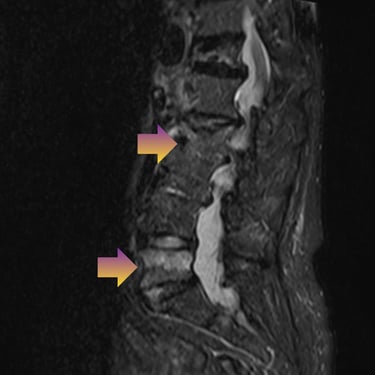

🧠Compresión medular cervical y dorsal: tratamiento mediante artrodesis y descompresión nerviosa.

La compresión medular cervical y dorsal es una patología grave que puede ocasionar déficit neurológico progresivo. La descompresión quirúrgica asociada a artrodesis vertebral permite liberar la médula espinal y estabilizar la columna, mejorando la función neurológica y evitando el deterioro clínico en pacientes adecuadamente seleccionados.